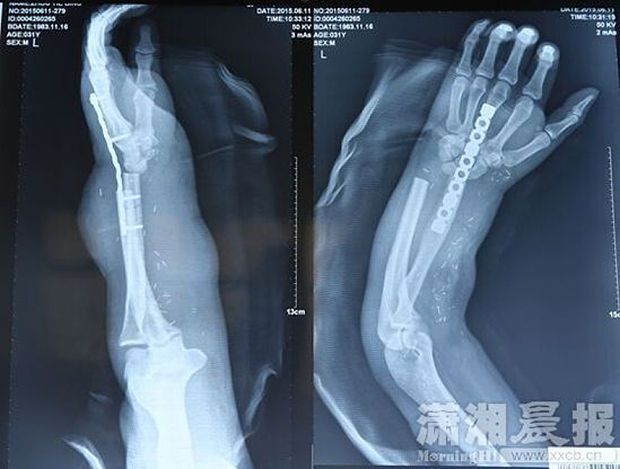

Очередным доказательством того, что медицина в современном Китае делает поразительные успехи, стала новаторская операция в клинике Xiangya города Чанша (провинция Хунань, Центральный Китай), в ходе которой оторванная при производственной травме рука пациента была пришита к его лодыжке на целый месяц.

Посовещавшись, медики приняли решение пришить руку к лодыжке пациента, чтобы она оставалась живой и восстанавливалась при этом в течении месяца, пока господина Чжоу готовили к заключительному этапу операции.

Издание пишет, что хирурги пришивали спасенную руку китайцу на протяжении 10 часов. Отмечается, что господин Чжоу может уже немного шевелить пальцами прооперированной руки. По словам хирургов, для полного восстановления пострадавшей конечности, мужчине требуется пройти длительный курс реабилитации.